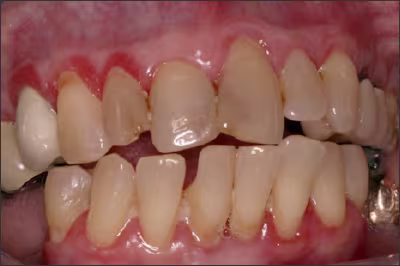

Periodontal Disease

To quote the 2014 Surgeon General’s report, “The evidence is sufficient to infer a causal relationship between smoking and periodontitis.”2 This was highlighted by Tomar and Asma, when they showed that 52.8% (8.1 million people) of periodontitis in the US population was attributable to current and former smokers.41 In addition, it was also demonstrated that quitting smoking reduced the risk of periodontitis.41

Given that the anchoring of a dental implant is achieved by osseointegration, and smoking is a risk factor for the destruction of soft and hard tissue that support the teeth, it is agreed that smoking increases the risk of implant failure.42-45